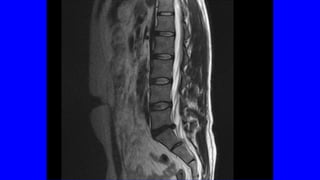

• ENCUESTA DE SALUD DEL INE: LA PREVALENCIA DEL DOLOR LUMBAR Y/O

CERVICAL EN ESPAÑA ES DEL 25% (> 10 MILLONES)

• PRIMER MOTIVODE CONSULTA MÉDICA • < 45 AÑOS ES EL PRIMER PROBLEMA INCAPACITANTE • EN EEUU ES EL MAYOR GASTO EN SALUD (IT, ANALÍTICAS, RX,RNM) • IMPLICA SUFRIMIENTO, DIFICULTAD PARA EL DESCANSO, TRISTEZA Y AL FINAL DEPRESIÓN: COMPONENTE PSICOSOCIAL • ENCUESTA DE SALUD DEL INE: LA PREVALENCIA DEL DOLOR LUMBAR Y/O CERVICAL EN ESPAÑA ES DEL 25% (> 10 MILLONES)